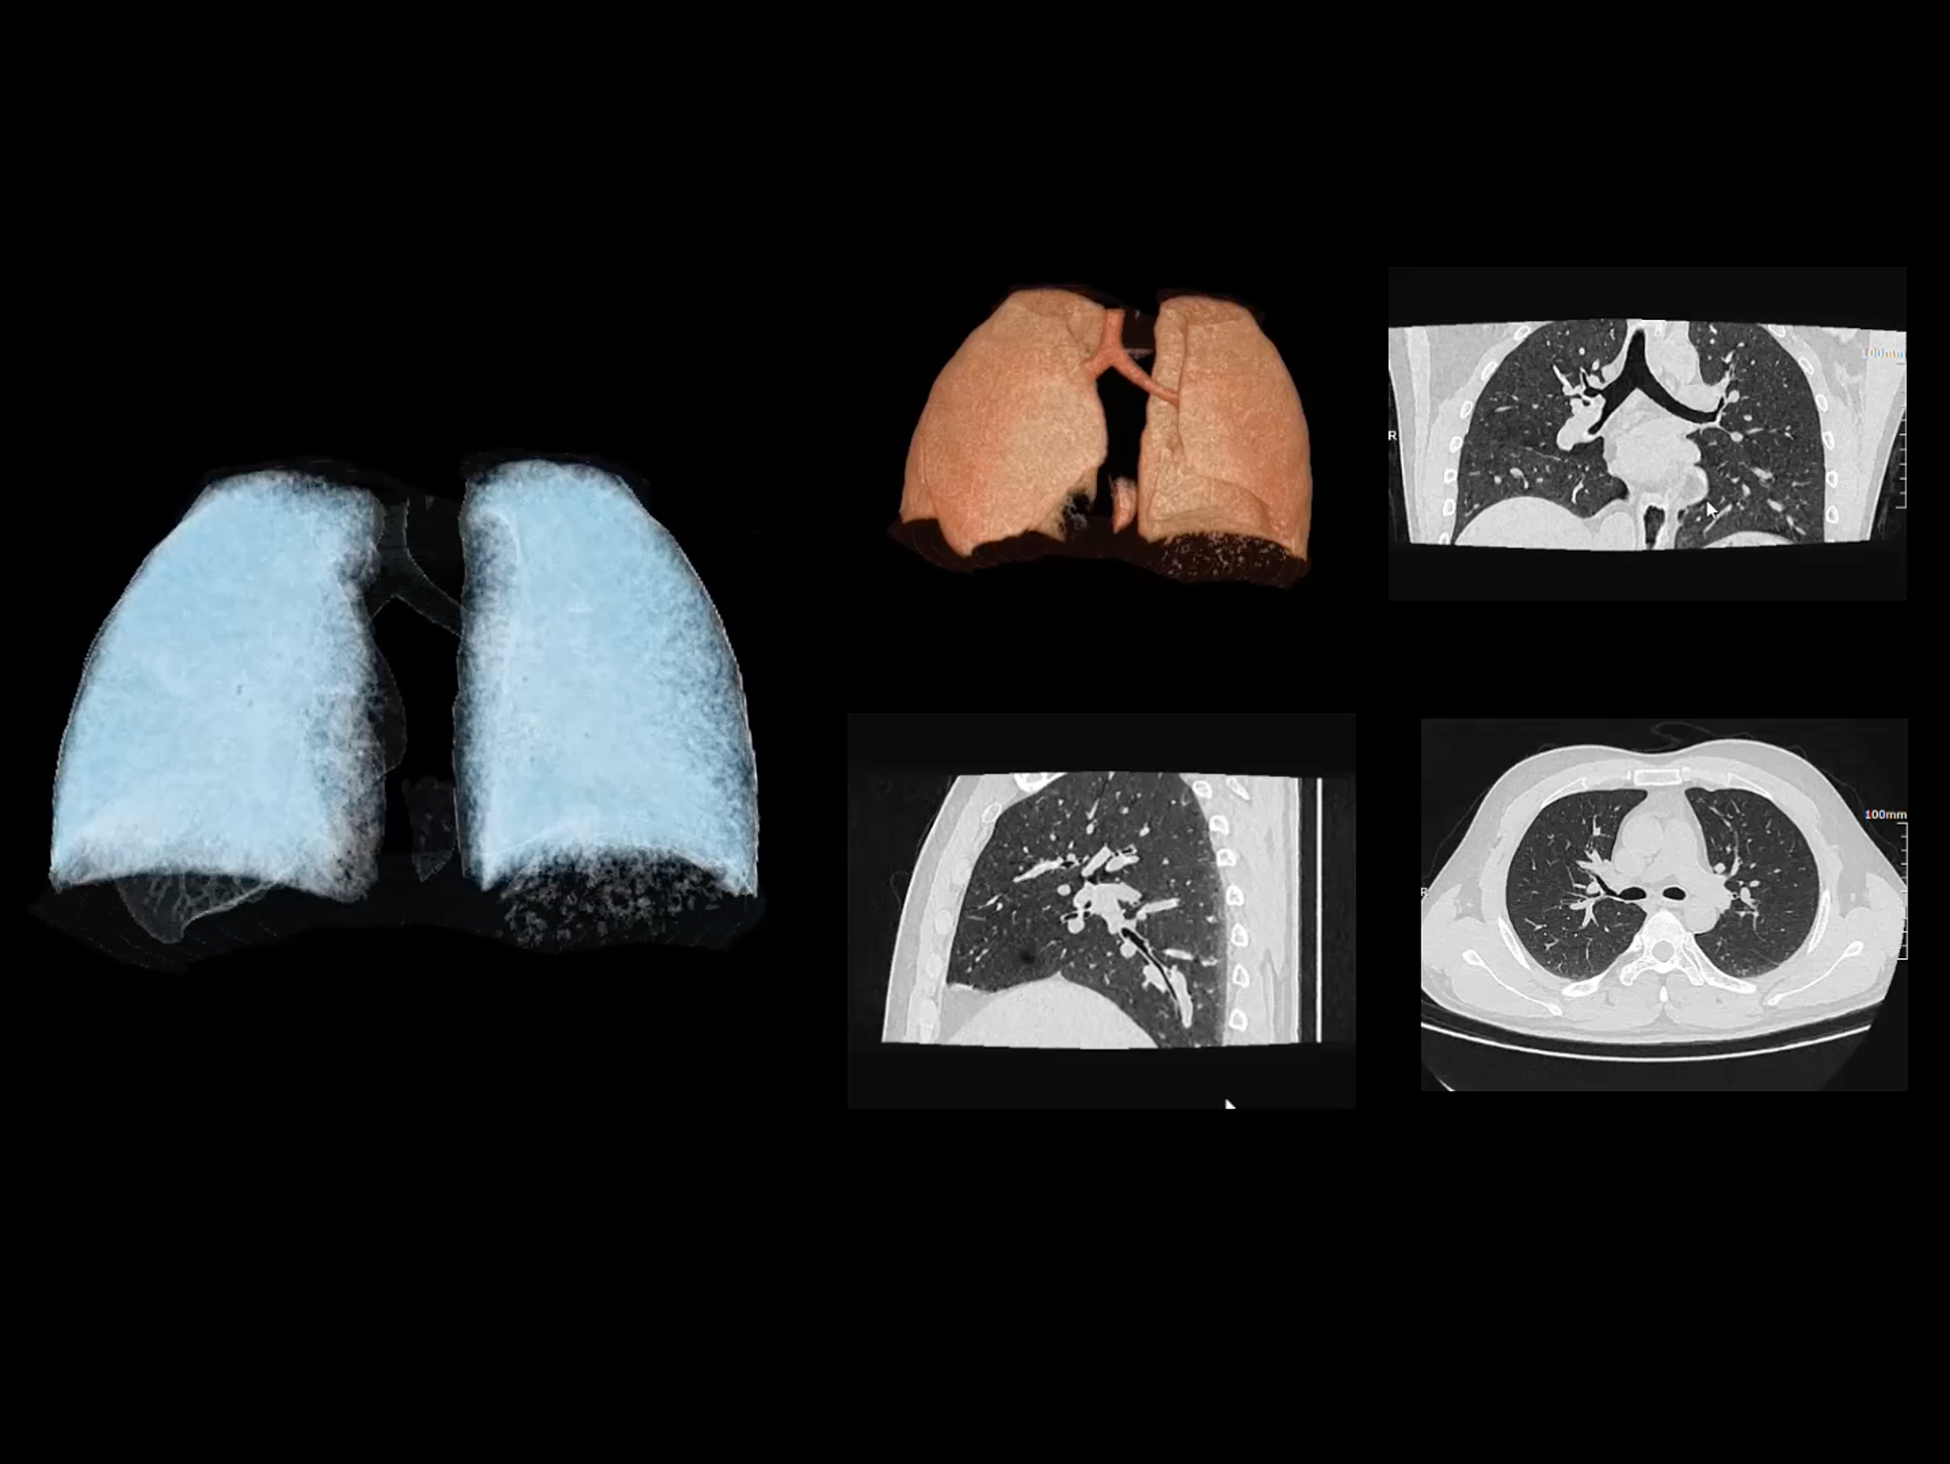

全域能谱

uCT SiriuX® 依托16cm超宽探测器与双源能谱技术,实现真正意义上的全身高清能谱成像。单次扫描同步获取灌注、能谱等多维定量参数,精准解析组织特性与病灶成分,为临床决策提供更深层次的诊断依据。

全身高清能谱成像

uCT SiriuX® 采用独有的双宽体探测器设计,实现470mm超大视野与全脏器容积覆盖的能谱成像,轻松应对不同体型患者和扫描部位应用需求。配合创新能谱重建影像链与精准双能数据配准,系统可有效抑制伪影、提升信噪比,在全脏器范围内提供高质量能谱图像,显著拓展临床精准诊断的广度与深度。

470 mm

• 双宽大视野

• 支持全身各部位能谱成像

SpeX

• 双能高精配准与硬化伪影校正

• 高清能谱分解&降噪重建技术

• 支持全身各部位、各类能谱成像

全面能谱分析工具

能谱成像可揭示丰富的物质与能量信息,其临床价值的充分释放有赖于完善高效的后处理分析平台。uCT SiriuX® 提供全面能谱高级分析工具,覆盖心血管、肿瘤、神经、骨科等多类临床场景。平台支持动脉增强分数分析(AEF)、细胞外容积分析(ECV)、肿瘤同源性分析、肺栓塞分析、骨髓水肿分析等多项评估,并提供多达10种基物质对成像,为精准诊断与科研探索提供坚实支撑。